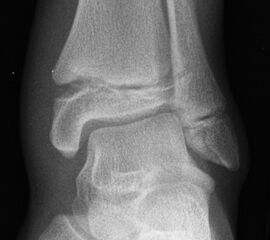

Fugengelenkfrakturen treten typischerweise vor dem 10. Lebensjahr auf, in einer Phase, in welcher die Wachstumsfugen noch weit offen sind. Dieser Frakturtyp betrifft fast ausschließlich den medialen Malleolus. Laterale Frakturen sind extrem selten, teilweise kommt es zu lateralen Bandverletzungen oder Fugenschaftfrakturen der distalen Fibula. Die Frakturlinie verläuft in einer Verlängerungslinie von der medialen Taluskante nach proximal. Häufig stellen sich Verletzungen des Innenknöchels im Röntgenbild schlechter dar, insbesondere wenn die Aufnahmen verdreht sind oder die Ebene der Fraktur bei geringer Dislokation verkippt zur Röntgenebene liegt. Besteht klinisch der geringste Hinweis auf eine Verletzung des Innenknöchels, muss aufgrund der Tragweite der Verletzung durch entsprechende Aufnahmen gegebenenfalls auch Schnittbildverfahren die Verletzung sicher diagnostiziert oder ausgeschlossen werden (Abb. 15).

„Kadiläsion“- Mediale Malleolarfraktur

Bei kindlichen Verletzungen des medialen Malleolus handelt es sich nach L. v. Laer um eine sogenannte Kadiläsion, d.h. eine Verletzung mit hohem Risiko eines schlechten Behandlungsergebnisses bei nicht korrekter Behandlung. Selbst bei optimaler Therapie ist das Risiko für spätere Wachstumsstörungen hoch, sodass diese Verletzungen nicht selten ein juristisches Nachspiel haben. Durch die Verletzung der wachstumsaktiven Zone kann es zu einem vorzeitigen Verschluss der Wachstumsfuge kommen, mit entsprechendem Fehlwachstum. Das Risiko eines vorzeitigen Verschlusses der Wachstumsfuge korreliert mit dem Ausmaß der Schädigung der wachstumsaktiven Zone. Ab dem 13. Lebensjahr wird das Risiko bei reduzierter Wachstumsaktivität zunehmend geringer.

Fugengelenkfrakturen können die Wachstumsfuge durchkreuzen (Abbildung 16a), ohne oder nur mit minimaler Beteiligung der Fuge sehr weit medial liegen (Abbildung 16b) oder durch die Fuge auslaufen (Abbildung 16c). Relevant für die Wachstumsprognose ist weniger die Form der Fraktur, sondern das Alter des Patienten zum Zeitpunkt des Traumas sowie das Ausmaß der Schädigung der Wachstumsfuge, wobei eine Korrelation mit dem Ausmaß der Dislokation besteht.